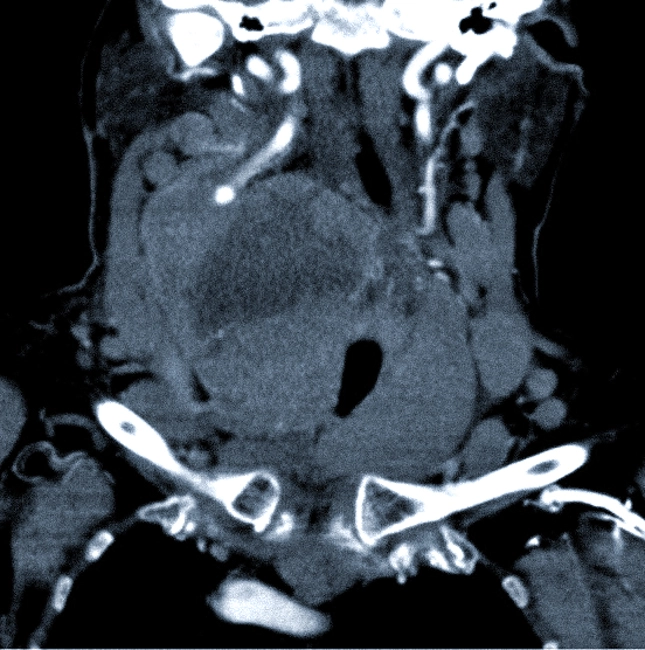

КТ щитовидной железы с контрастированием

Компьютерная томография щитовидной железы предполагает использование контраста, так как обычные снимки могут не предоставить полной картины о наличии узелков, сосудов и опухолей. Специальные йодсодержащие препараты вводятся внутривенно для улучшения визуализации: они быстро наполняют сосудистую сеть и подчеркивают патологически измененные участки на томограммах.

Если есть подозрение на наличие новообразований, врач может назначить КТ с контрастом. Контраст — это безопасное йодсодержащее вещество, которое позволяет лучше визуализировать кровеносные сосуды. Благодаря этому препарату новообразования становятся более заметными на снимках благодаря наличию большого количества сосудов.